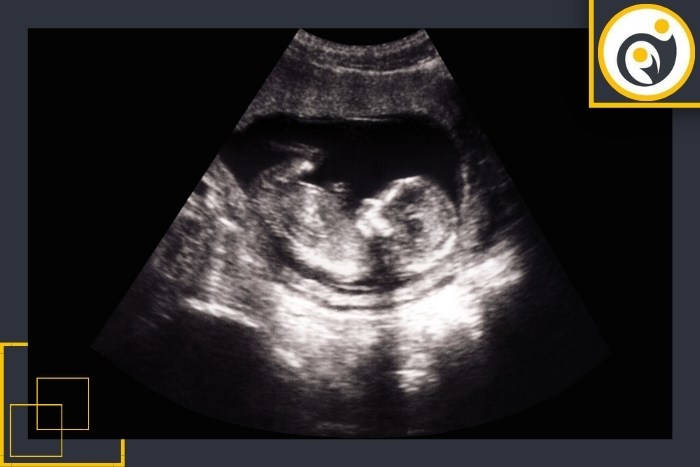

تفاوت سونوگرافی ترانس واژینال و شکمی در اوایل حاملگی

نحوه انجام:در این روش مبدل مخصوصی (پروب سونوگرافی) وارد واژن میشود. امواج صوتی با فرکانس بالا از طریق این پروب به بافتهای لگن ارسال و تصویر دقیقی از رحم، تخمدان، لولههای فالوپ و جنین اولیه ایجاد میشود.

روش انجام:در این نوع سونوگرافی بیمار روی تخت دراز میکشد و ژل مخصوص روی شکم او زده میشود. سپس پزشک با حرکت دادن پروب روی ناحیه تحتانی شکم تصاویر را بر روی مانیتور مشاهده میکند.